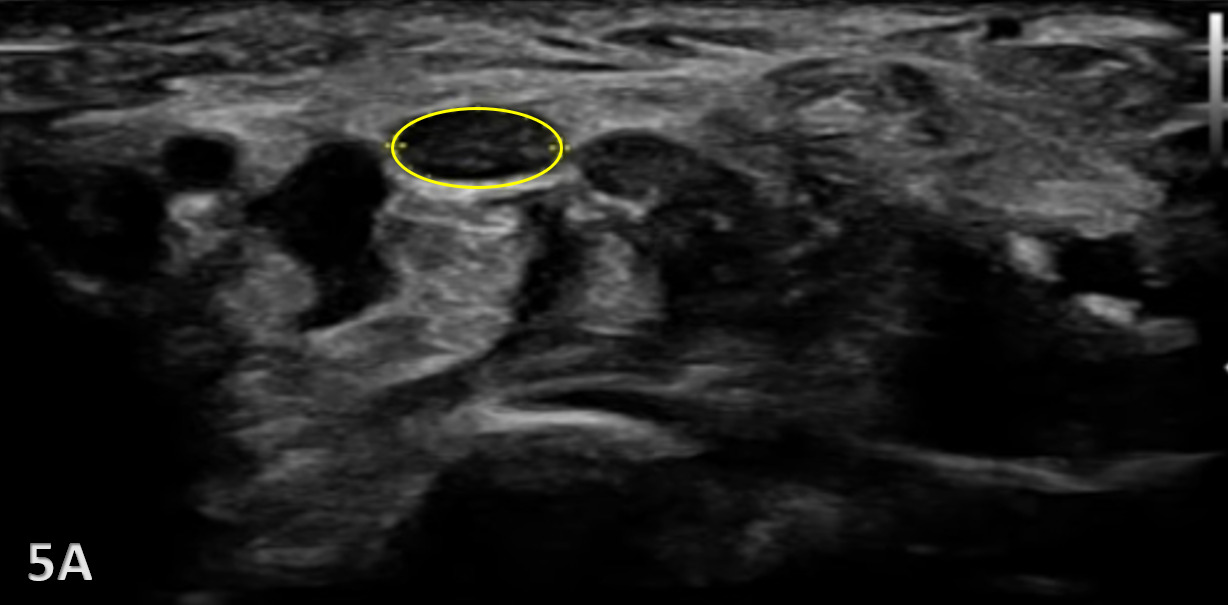

The median nerve is clearly identifiable in SAX by a well circumscribed ovoid structure with hypoechoic fascicles in a honeycomb-like pattern deep to the roof of the carpal tunnel, the flexor retinaculum, and more superficial to the flexor digitorum superficialis and flexor digitorum profundus tendons. The median nerve is also very compressible and will alter its shape depending on the volume of the anatomical spaces with which it courses. The median nerve cross-sectional area (CSA) can be measured in four sites: 1) the proximal border of the pronator quadratus muscle, 2) proximal to the carpal tunnel inlet, 3) at the tunnel inlet, and 4) at the tunnel outlet.9

Pathological Findings in Median Nerve Pathology at Wrist

A maximal CSA of 12 mm2 or greater at any location is typically diagnostic for CTS.6 More recent evidence shows that CSA may vary based on subgroupings including age, sex, ethnicity, geographical location, and method of CSA assessment.10 An increase in size greater than 2 mm comparing proximal (at pronator quadratus) to distal (at wrist crease) can diagnose carpal tunnel syndrome with 99% accuracy.11

Carpal Tunnel Syndrome can be identified by the following images:

Hypoechoic thickening due to swelling and edema

Disruption of fibrillar pattern

Associated joint effusion